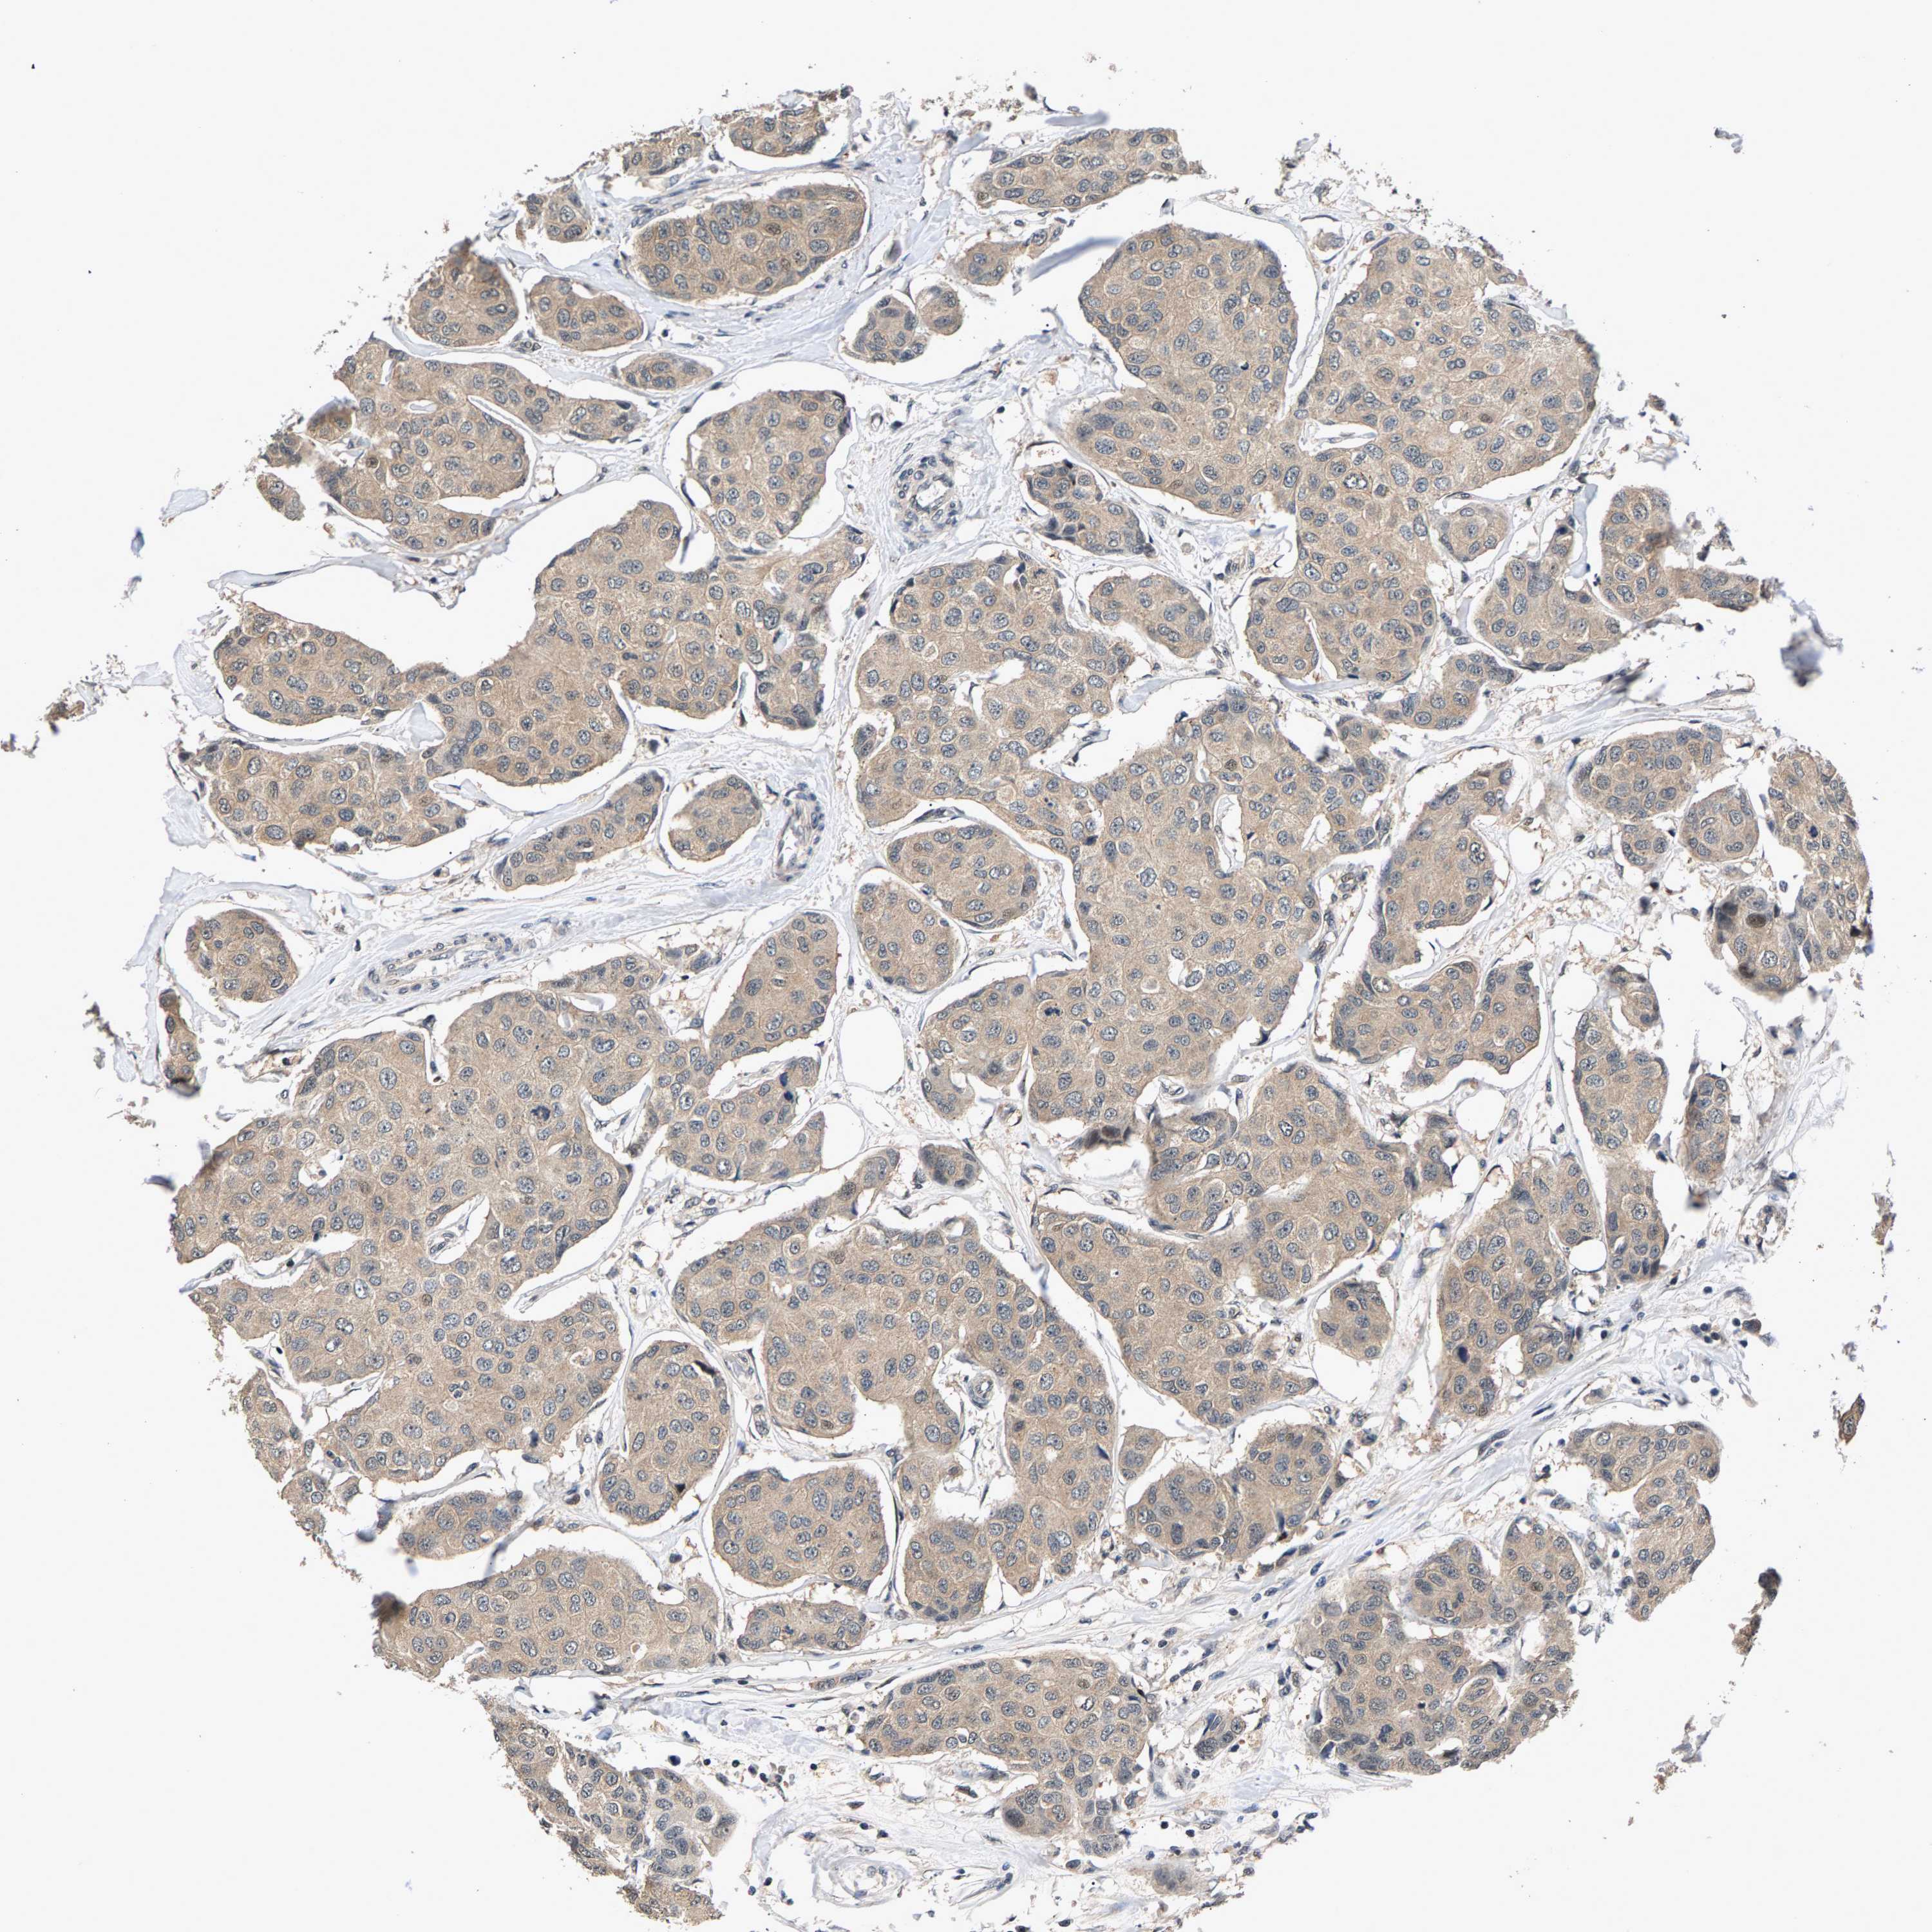

CANCER BREAST CANCER Show tissue menu

BRCA TCGA BRCA VALIDATION PROTEIN EXPRESSION